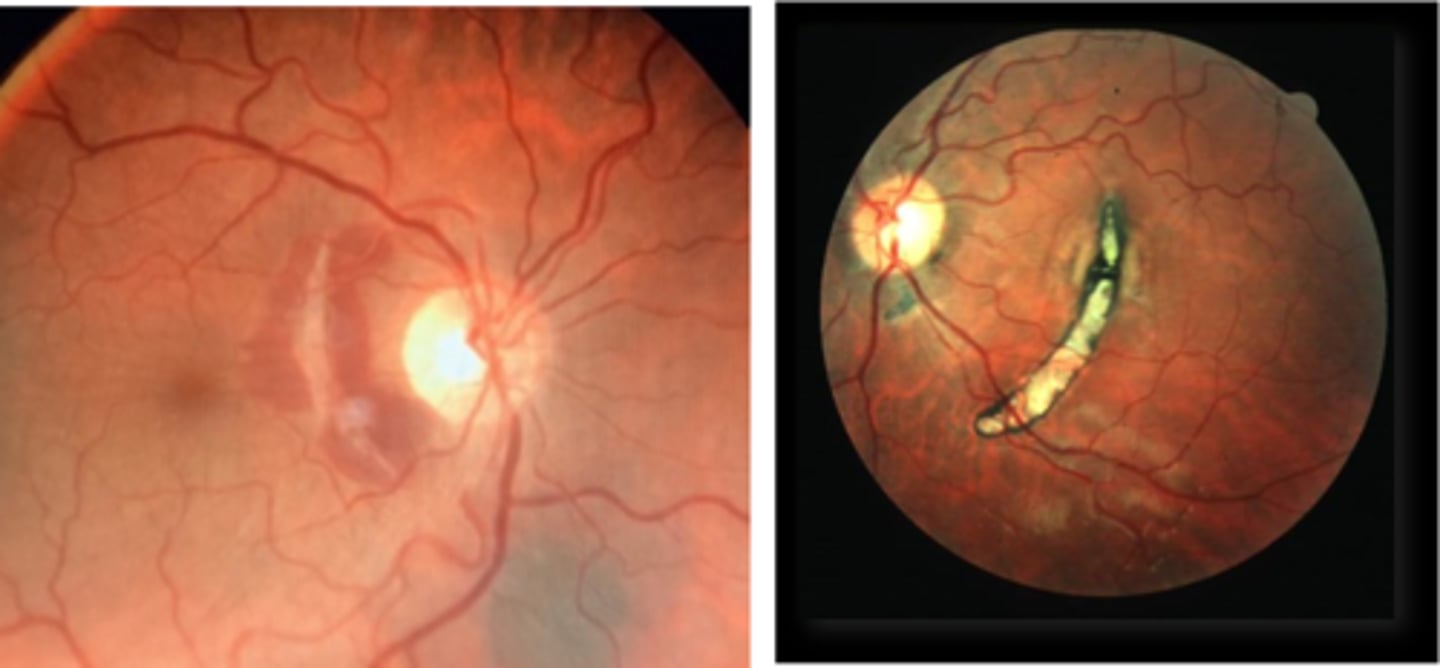

How does choroidal rupture appear on fundoscopy?

curvilinear or crescent-shaped streak, sometimes concentric to ONH

+/- subretinal /subRPE hemorrhage (acute)

Bruch's/Choriocapillaris/RPE damage

overlying neurosensory retina is intact

+/- RPE hyperplasia (chronic)

+/- CNV over time

What findings of degenerative myopia are seen here?

PPA

crescent

lacquer cracks

How do lacquer cracks appear on fundoscopy?

jagged, irregular yellow lines showing sclera in the posterior pole